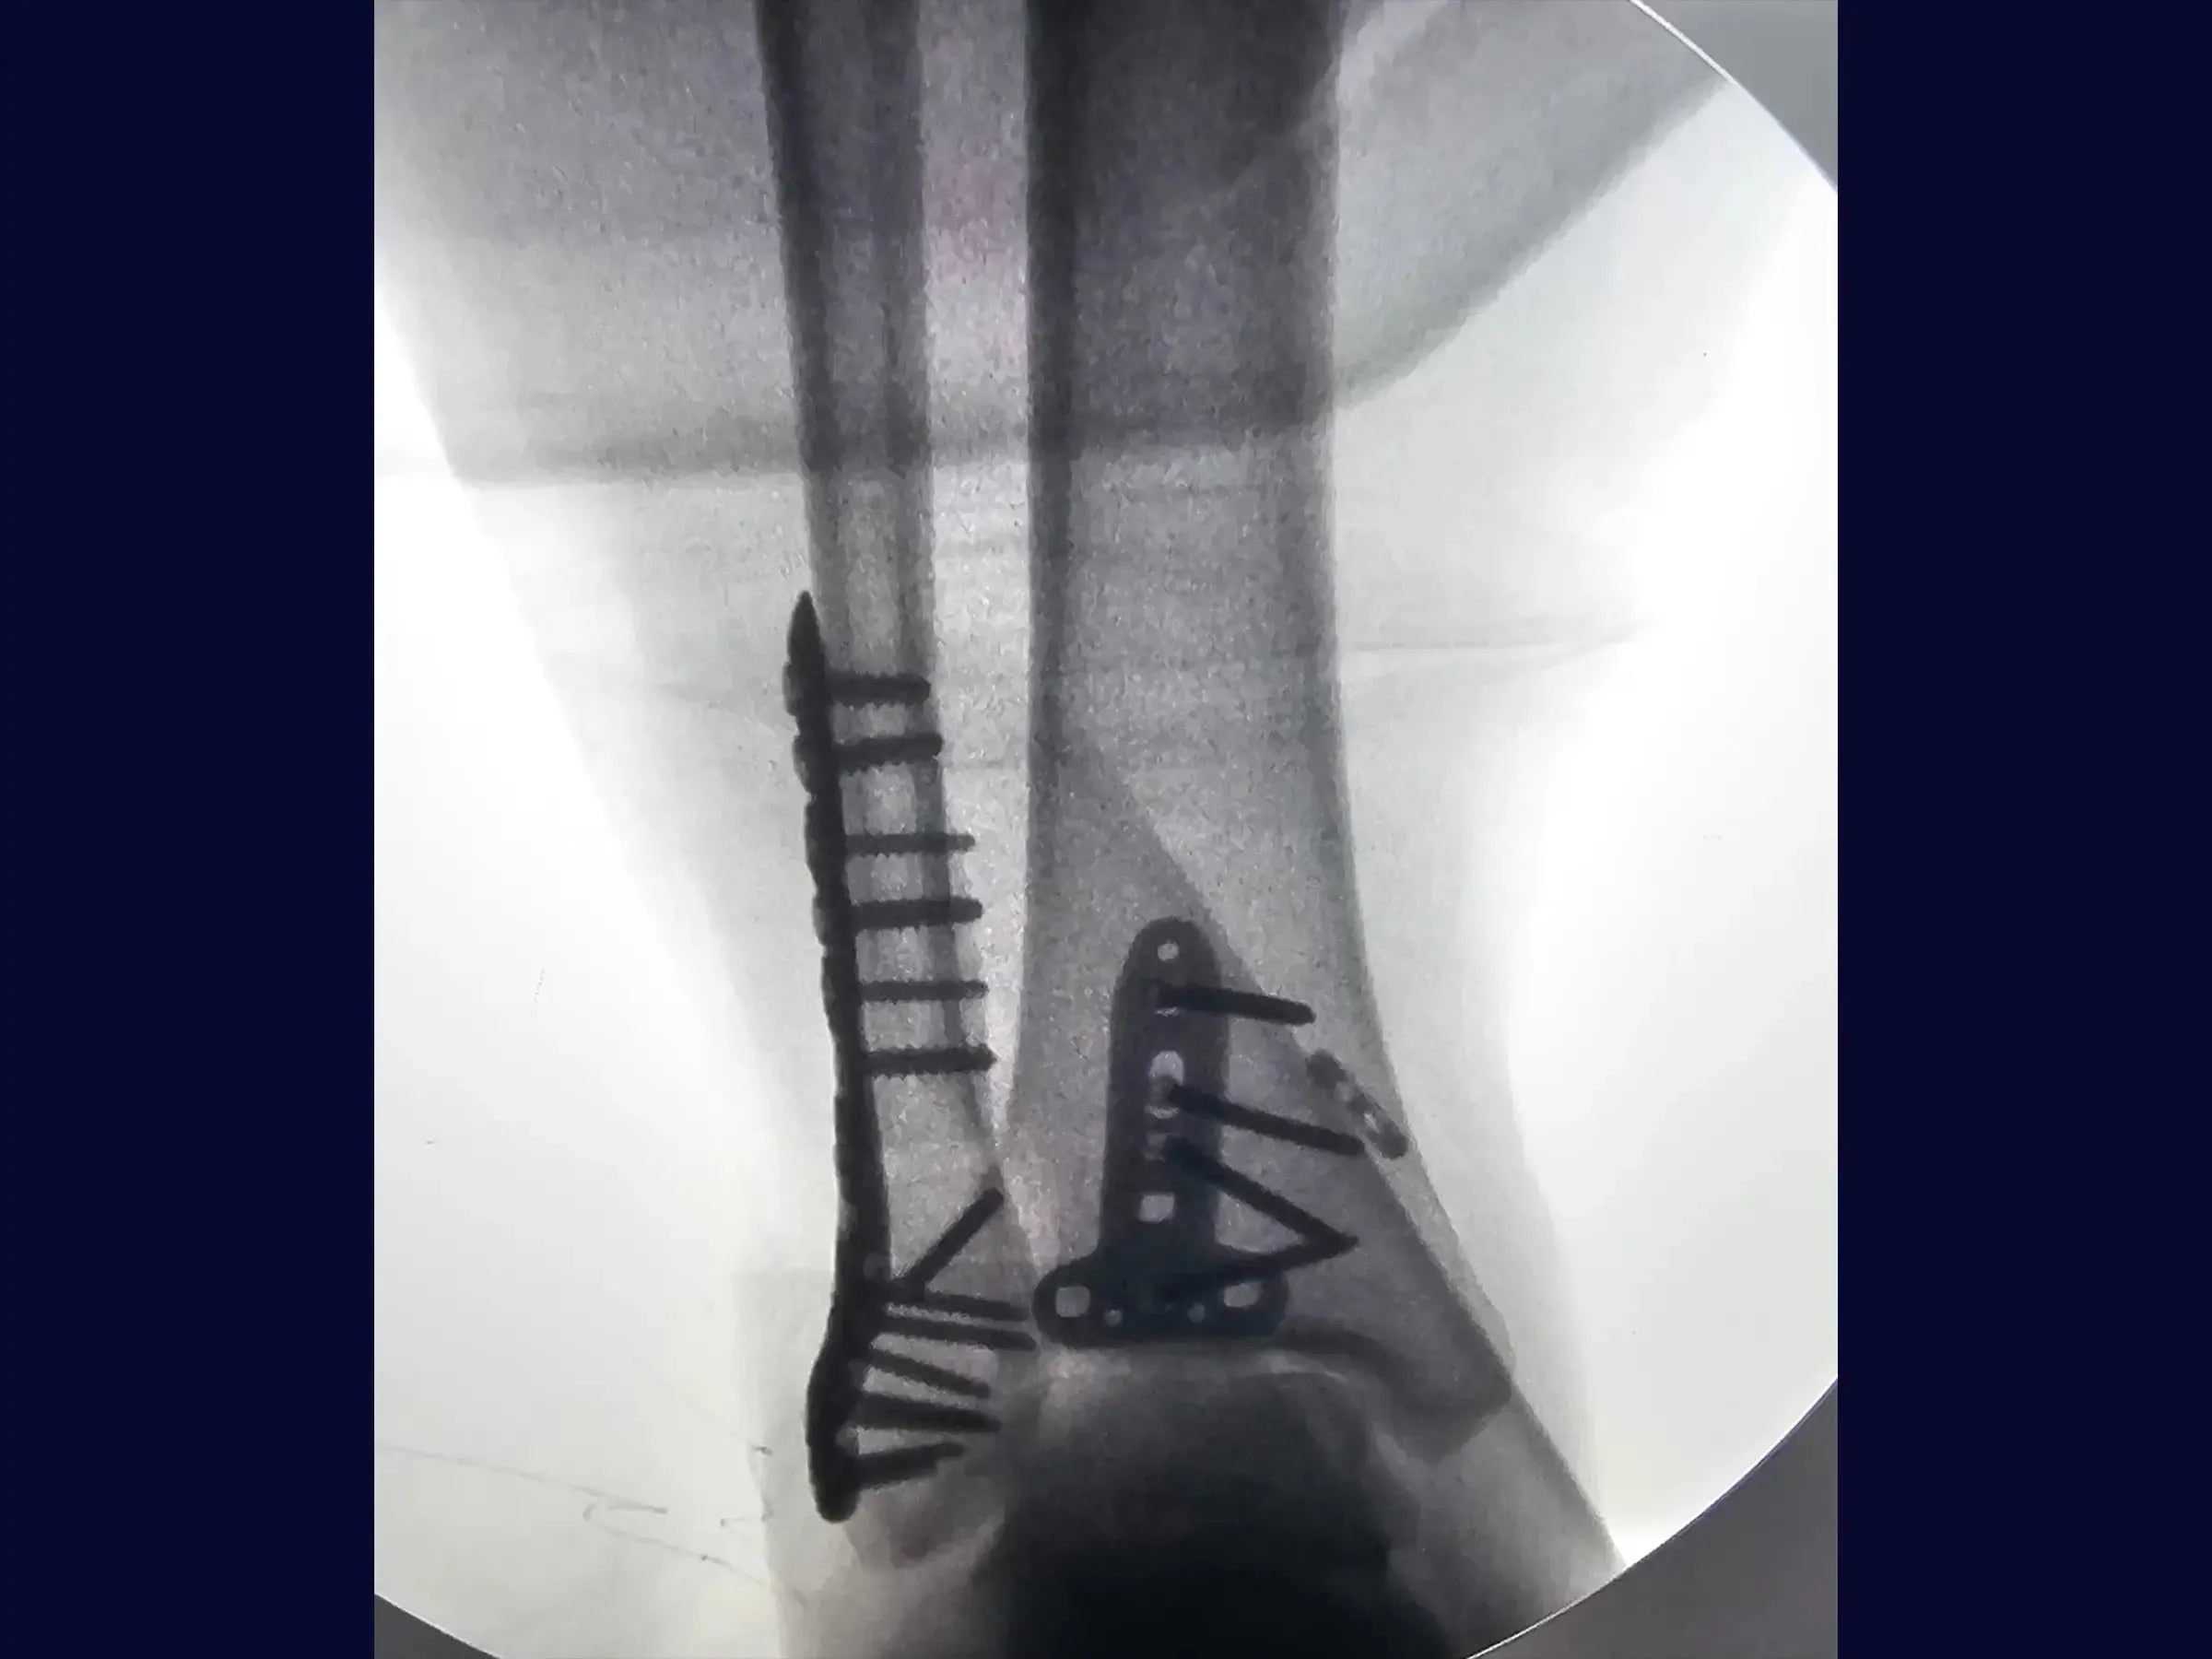

Fractura del maléolo posterior y del maléolo lateral (abordaje posterolateral único)

Dominar el abordaje de fracturas complejas de tobillo supone un reto técnico para los cirujanos ortopédicos. Esta formación proporciona una inmersión técnica en el tratamiento de fracturas de maléolo posterior asociadas con fracturas de maléolo lateral alto, mediante un abordaje posterolateral curvo único y técnicas de reducción indirecta.

- Tratamiento quirúrgico de la fractura de maléolo posterior y fractura de maléolo lateral alto del peroné.

- Utilización de abordaje posterolateral de curva única.

- Técnica de reducción indirecta del maléolo posterior.

- Fijación con tornillos interfragmentarios y placa bloqueada.

- Fijación Estable del Maléolo Lateral: Secuencia para fijación provisional y definitiva con tornillos interfragmentarios y placa bloqueada, evitando tornillos articulares.

- Acceso Directo al Maléolo Posterior: Método para abordar el maléolo posterior a través del mismo acceso, rompiendo la fascia y reflejando los tendones para su visualización.

- Reducción indirecta efectiva del maléolo posterior: demostración de la técnica de reducción indirecta del maléolo posterior mediante la acomodación de la placa y la introducción de tornillos, minimizando la exploración.